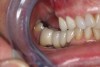

After 2 weeks, excellent soft-tissue healing and maintenance of the labial gingival tissue was evident. The same was true after 3 months (Figure 21). The gingival zenith continued to be maintained after 1.5 years (Figure 22). Importantly, the facial wall bone thickness of the implant also was maintained at the 1.5-year follow-up (Figure 23), suggesting favorable maintenance of this case.

Fig 21. Soft-tissue healing after 3 months. Note maintenance of the facial gingival zenith.

Figure 21

Fig 22. Final restoration after 1.5 years. Note the soft-tissue contour on the buccal aspect.

Figure 22